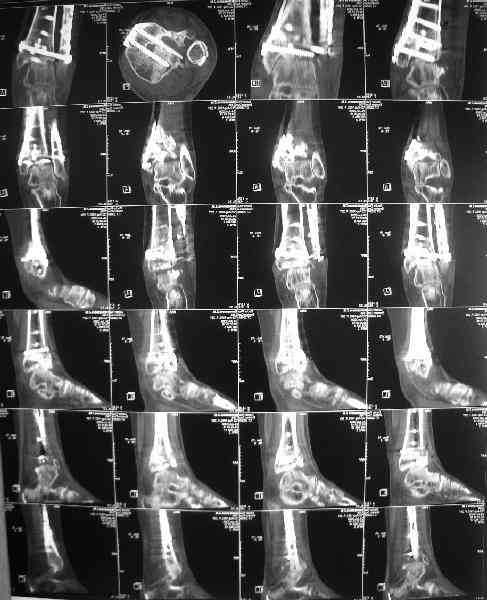

Dear коллеги,Обратилась женщина, 25 л. 8 мес. назад в одной из больниц сделан остеосинтез пилона. На сегодня ходит без дополнительной опоры, хромая на поврежденную ногу. Движения в голеностопном суставе еще есть. Снимки в приложении.

A female, 25, 8 month ago operated elsewhere. To date walks without support with pain and limp. The ankle is mobile yet. Images attached.The question is what to do now? The patient is not very keen on ankle fusion (though likely could change her mind if necessary)Is it worth to try a reconstruction procedure and what kind? Maybe it allows to restore alignment and tibio-fibular relationship - will it provide painless limb for more or less significant time?Or just remove the hardware and leave her alone until she herself comes for fusion?

She has an intraarticular screw on CT, best is to remove all and wait untill she asks for fusion.

CT images/xrays confirm incongruity of articular surfaces as well as intraarticular screws.

removing just those screws which have penetrated the joint may take some pain away.

Александр, добрый вечер! К сожалению, боюсь, что, кроме артродеза, ничего не осталось, упущено время. Просто убрать железо конечно можно, а куда деть вальгусную установку, "синдесмоз", признаки артрофиброза, которые прослеживаются на представленных рентгенограммах. Вопрос же стоит в качестве жизни пациентки, может ей тактично все объяснить, что чем дольше она будет так ходить, тем возможно болевой синдром будет более стойким и усилится деформация.